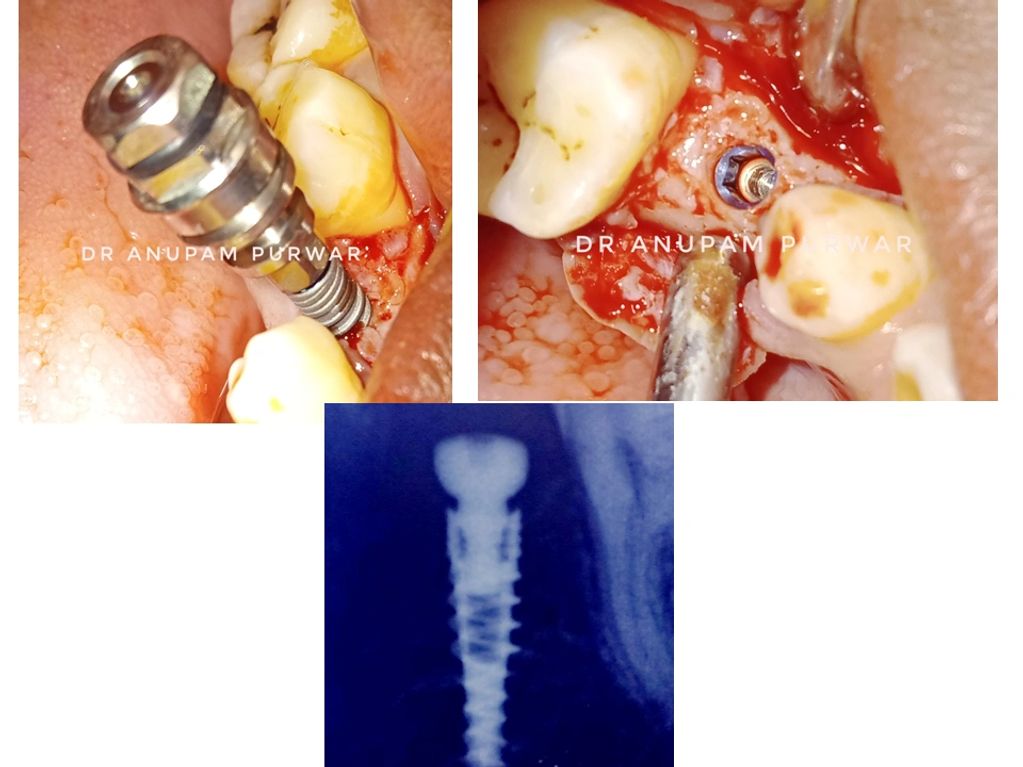

1. Single Implant Placed in Lower Jaw

2. Four Implants placed in Lower Jaw

3. Two Implants placed in Lower Jaw

4. Two Implants placed in Lower Jaw

5. Single Implant Placed in Lower Jaw.

6. Single Implant placed in Lower Jaw.